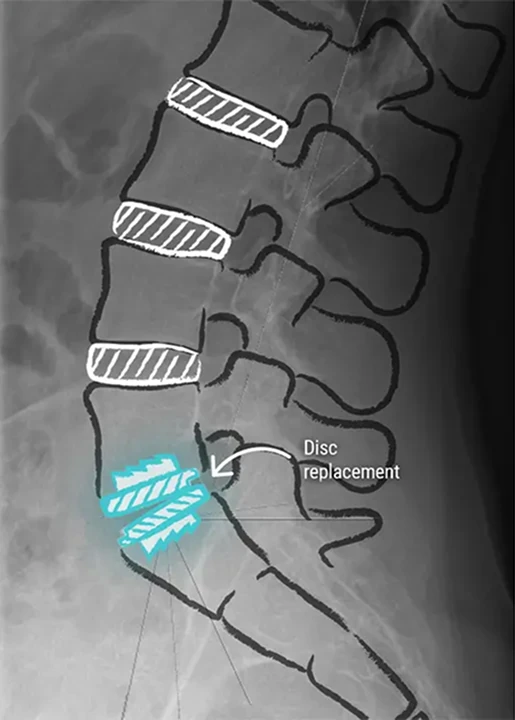

Annotated lumbar spine MRI showing a herniated disc with dehydration and protrusion compressing spinal nerves, compared with normal healthy discs.

SpinePro, in conjunction with CCV Montpellier, offers Prodisc® L total lumbar disc replacement, a minimally invasive surgical procedure which fully restores spinal mobility and permanently relieves symptoms in a single procedure by safely replacing the degenerated natural disc with an artificial disc.